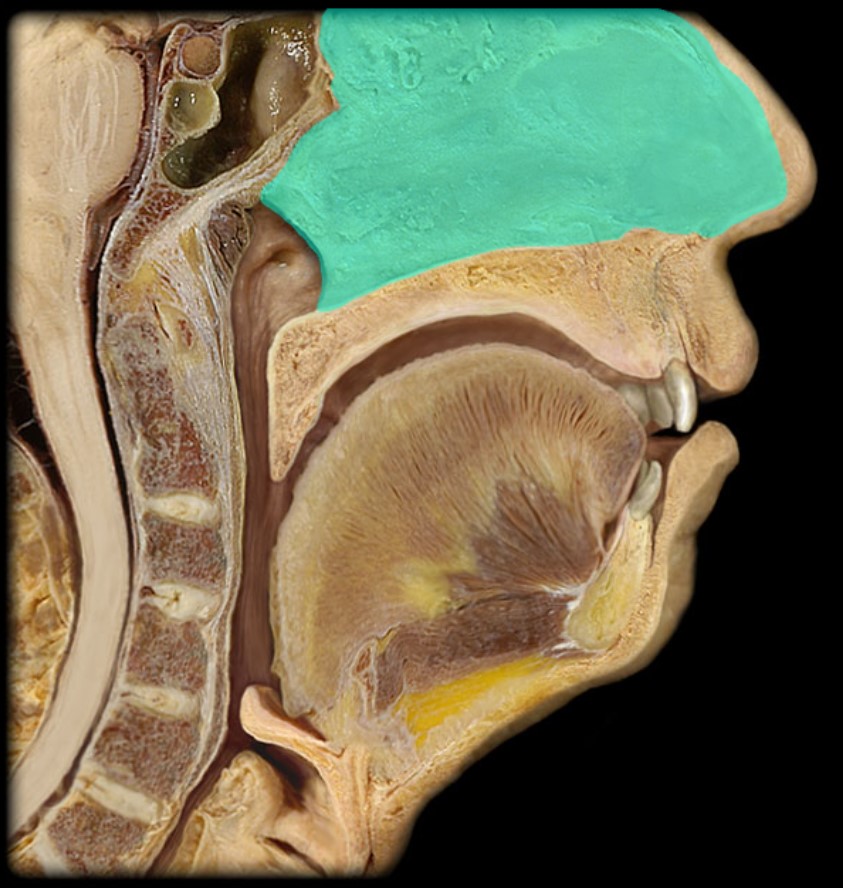

Nasal Septum

(Donor Only)

Esophagus

Trachea

Vocal Fold

Epiglottis

Mylohyoid

Geniohyoid

Genioglossus

Lingual Tonsil

Palatine Tonsil

Uvula

Soft Palate

Palatine Bone

Maxilla

Pharyngeal Tonsil

Auditory Hiatus

Torus Tubarius

Sphenoid Sinus

Inferior Nasal Concha

Middle Nasal Concha

Superior Nasal Concha

Nasal Vestibule

External Nares

Frontal Sinus